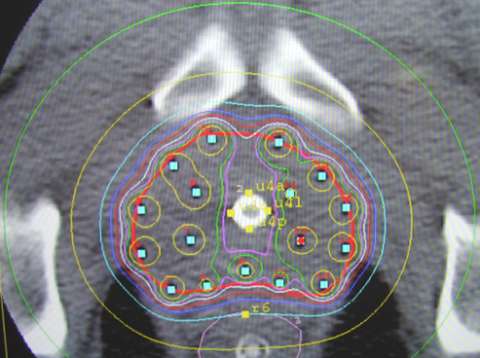

- The physician then uses a template to help direct the treatment tubes called "flexiguides" in and around the prostate. This template has pre-drilled holes arranged in two concentric circles. This circular distribution conforms better to the natural shape of the prostate. The template is held in one hand, while the flexiguides are inserted with the other. Holding the template, rather than having it clamped to the table as in the fixed template technique, allows the physician to tip and angle the template, resulting in more control over where they can place the flexiguides. This is a major advantage as it allows the physician to flare the flexiguides to encompass larger prostates, extracapsular extension, or seminal vesicle involvement.

Below is an example of the standard template that we use for prostate brachytherapy here at UCLA.

Once the flexiguides are in position the template is sutured to the perineum to stabilize the implant.